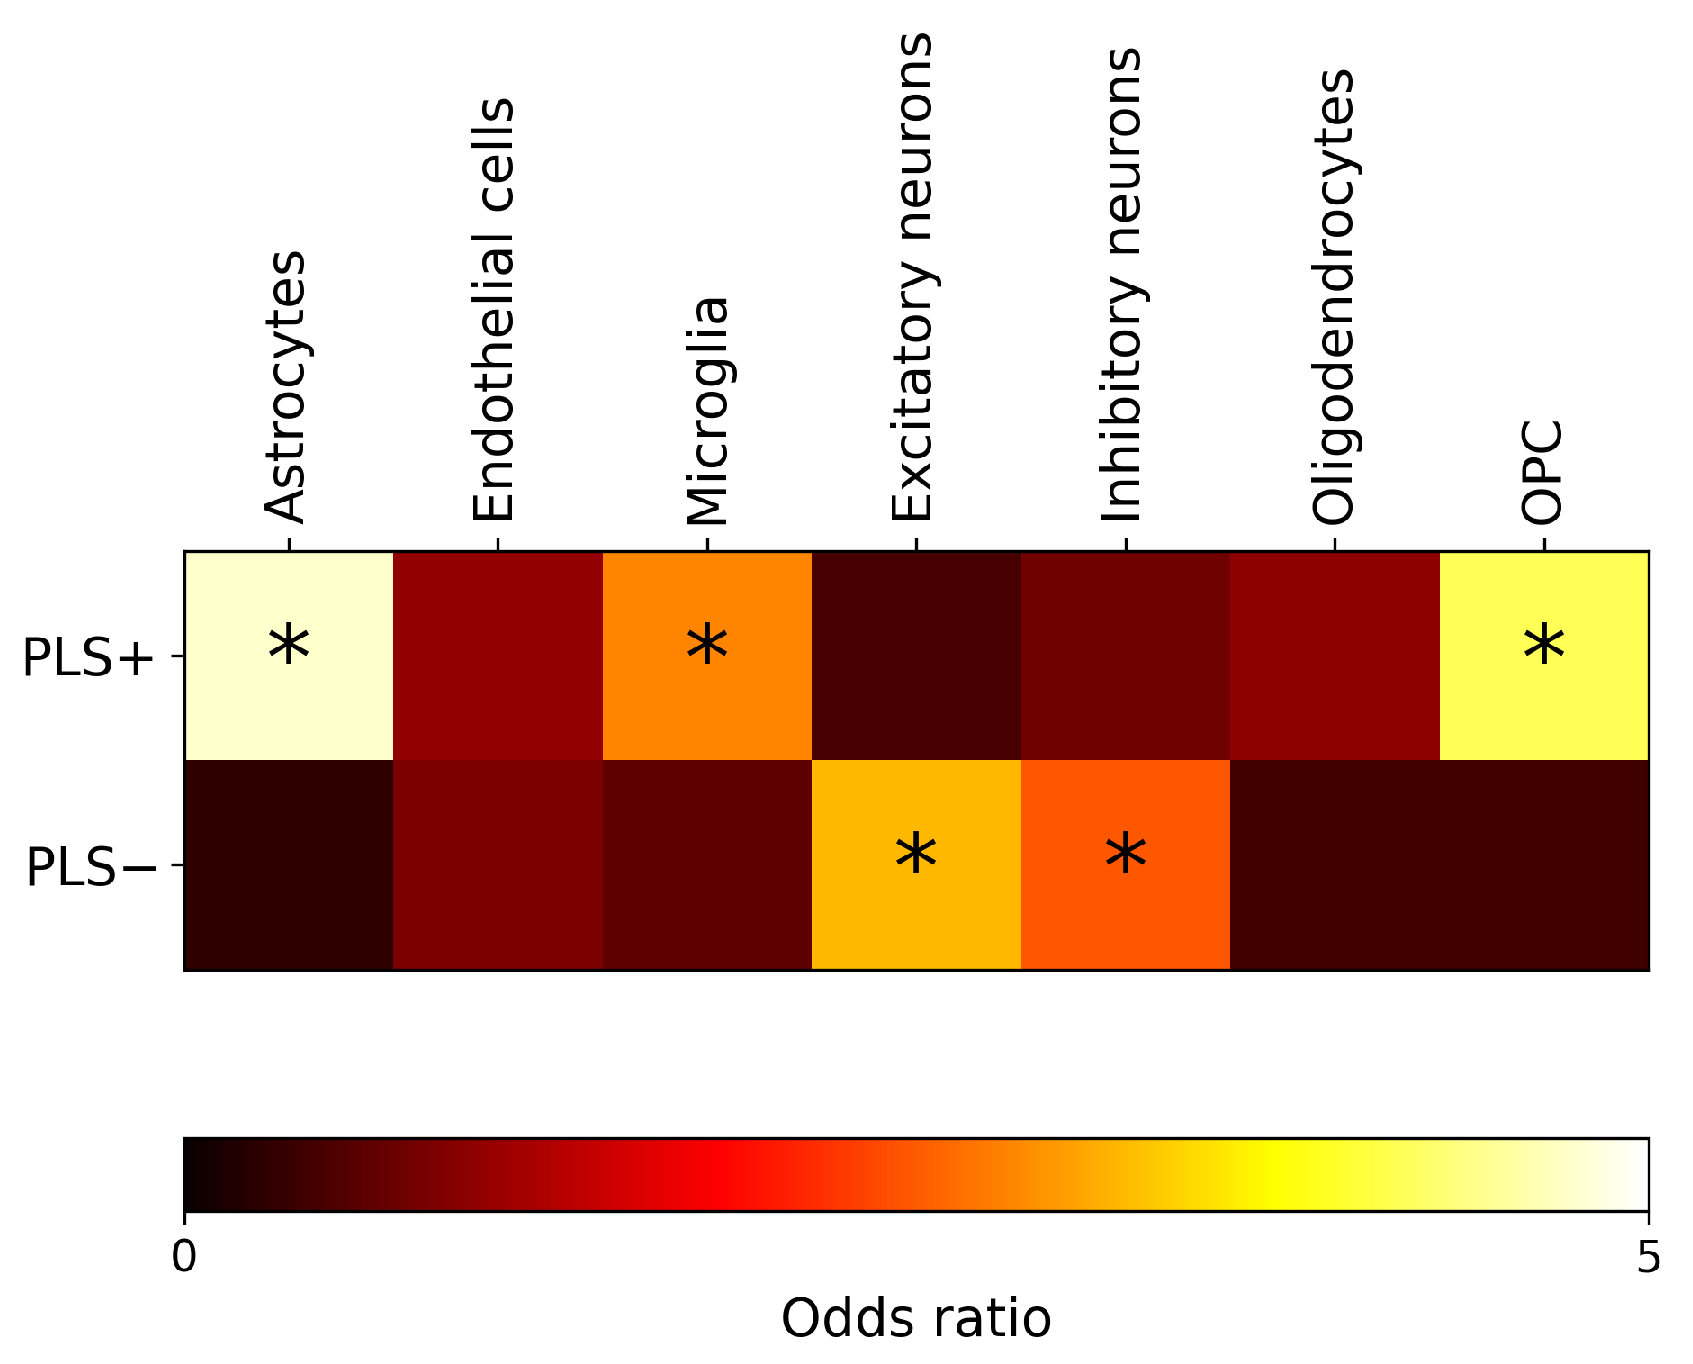

2.3. Enrichment Analysis